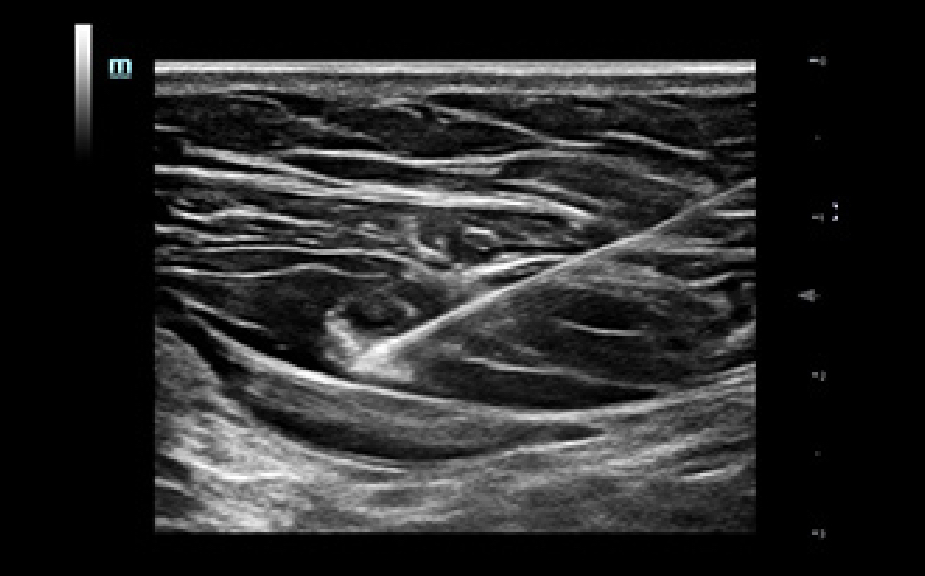

Single Operator Puncture Solution

Images